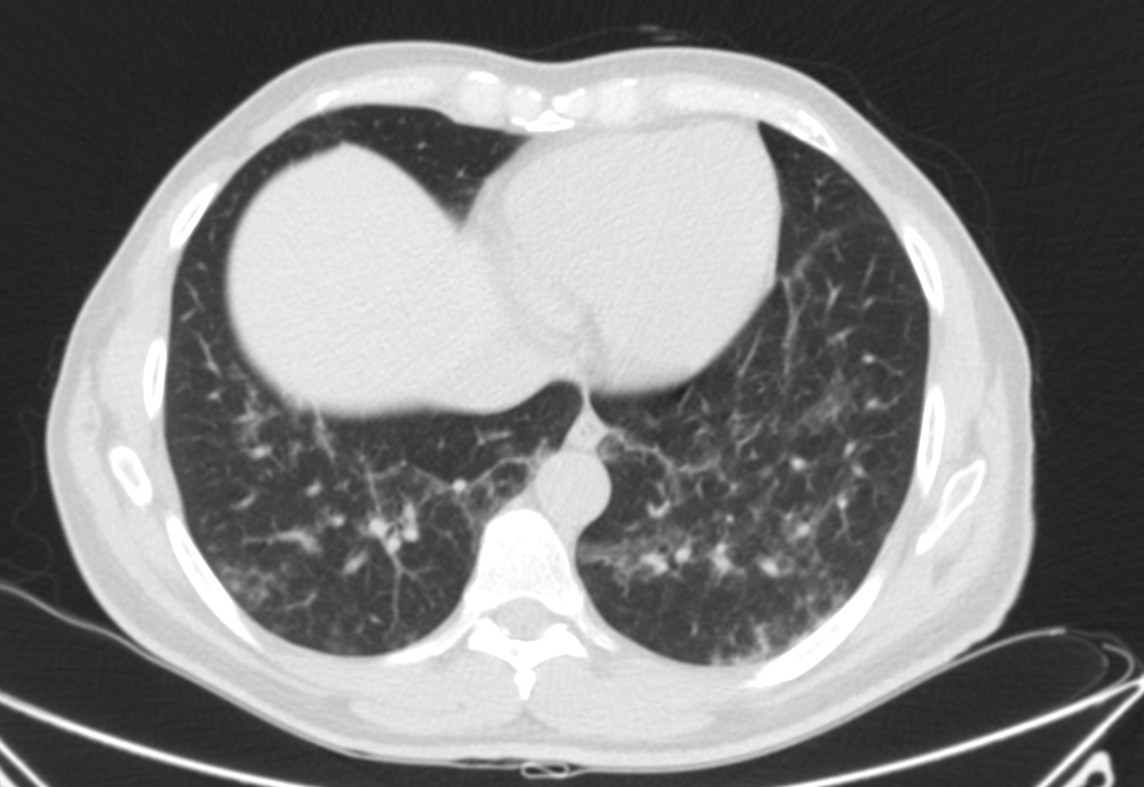

Describamos los hallazgos:

TAC: Vidrio deslustrado difuso y perihiliar frecuente, infiiltrado reticular, consolidaxión y patrón de árbol en brote, engrosamiento de septos, patrón en empedrado, derrame pleural, quistes.